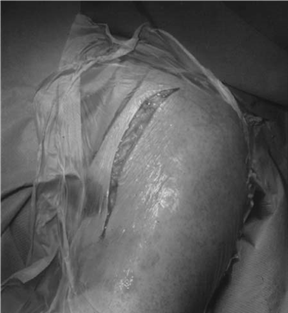

Can you describe the deltopectoral approach to the glenohumeral joint?

General anaesthetic ± interscalene block.

Beach chair position.

I ncision is from 1–2 cm inferior to the tip of the coracoid process extending towards the anterior axillary fold. The deltopectoral groove is identifi ed by a ‘yellow stripe’ of fat and the cephalic vein is sought lying in the groove. The vein is usually refl ected laterally. The interval between the deltoid and the pectoralis major is developed and the conjoined tendon arising from the coracoid process is identifi ed. The conjoined tendon is now dissected free from the underlying subscapularis. The conjoined tendon is retracted medially with the help of the self-retaining retractors ( ± partial division 1 cm distal to the coracoid). The subscapularis muscle and its tendon are identifi ed by externally rotating the arm. Stay sutures are used to control the medial musculotendinous tissues of the subscapularis. With the arm in ER, division of the subscapularis tendon is carried out about 1–2 cm from its insertion just lateral to the musculotendinous junction. Depending on indication, the subscapularis muscle is then either stripped off the anterior capsule or the capsule is divided with the tendon.

Nerves at risk

zThe axillary nerve lies just inferior to the shoulder joint capsule. A blunt ring-handled retractor is slipped down on the anterior capsule and passed inferior to the shoulder, retracting the inferior structures including the axillary nerve away from the capsule, thereby protecting this important nerve which lies only 5–10 mm below the inferior capsular fold

zThe musculocutaneous nerve